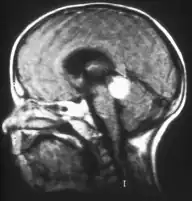

El retinoblastoma tiende a extenderse hacia el cerebro y la médula ósea, y más raramente se disemina por los pulmones. Estos son factores de pronóstico adverso, así como la invasión coroidal y a través del nervio óptico.[1]